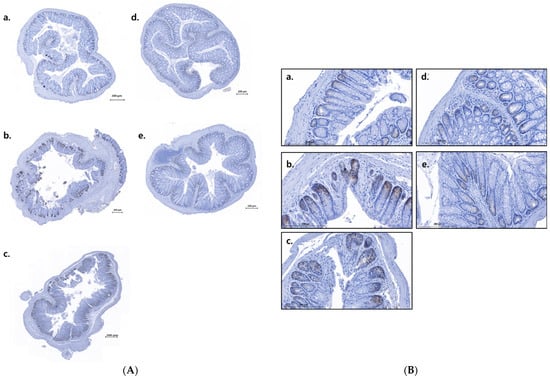

3.2.4. Effect of LNL on Claudin-2 Expression in Mouse Colon Tissue

| NC | OXAC | LNL 40 | LNL 80 | ME | |

|---|---|---|---|---|---|

| Totalarea (μm2) | 1,433,933.28 | 3,065,461.29 | 2,546,376.58 | 2,375,414.46 | 2,208,251.85 |

| claudin-2area (μm2) | 24,089.25 | 95,752.78 | 66,821.68 | 35,863.96 | 33,907.18 |

| claudin-2area (%) | 1.68 | 3.12 | 2.62 | 1.51 | 1.54 |